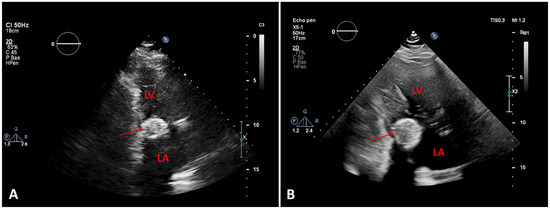

Myocardial infarction with nonobstructive coronary arteries (MINOCA): Myocardial infarction (MI) with non-obstructive coronary arteries (MINOCA) is defined as MI according to the fourth universal definition of MI [1] without coronary stenosis ≥50% on...